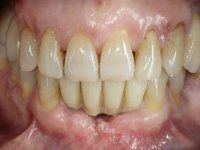

Após estudo imagiológico foi planificada a colocação de dois implantes de 3.3 mm de diâmetro e 10 mm de comprimento. No dia da cirurgia foram extraídos os dentes 42 e 32 e removido o implante. Os implantes foram colocados na zona dos alvéolos tendo o cuidado de lingualizar um pouco o seu posicionamento. Foi feita uma impressão pela técnica de moldeira aberta com o retalho aberto para a confeção da ponte provisória imediata. Enquanto a impressão foi para o laboratório, foram colocados parafusos de cicatrização altos e feita a sutura da ferida cirúrgica. A paciente esperou 2 horas na sala de espera enquanto no laboratório era confecionada a ponte provisória. A ponte provisória imediata aparafusada foi colocada e o seu assentamento controlado imagiologicmente. Passados 3 meses foi realizada a impressão definitiva com uma técnica de moldeira aberta. Nessa consulta aproveitamos para polir a ponte provisória com taças de borracha para que os tecidos moles pudessem maturar em melhores condições. Foi feita a recolha de informação para caracterizar da melhor forma a estrutura monolítica em Zr. Foram utilizadas guias de cor para a cerâmica de tonalidade coronária e gengival. No laboratório foi confecionada uma ponte em Zr. aparafusada que foi cuidadosamente caracterizada. Após aprovação pela paciente foi colocada definitivamente em boca. O aperto foi feito com uma chave dinâmica com 35 N de torque. Os orifícios foram tapados com teflon e obturados com resina composta.